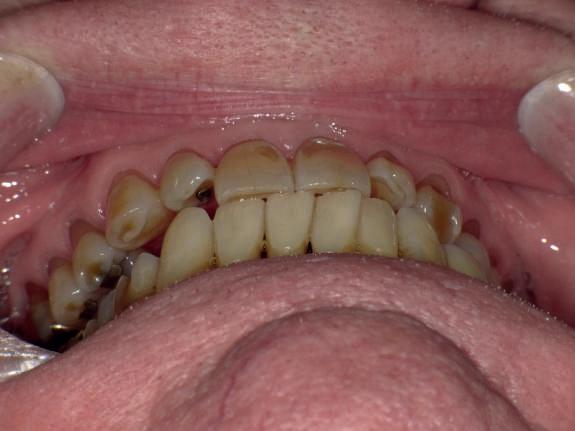

Examinarea parodontală a relevat sângerări generalizate la sondare și adâncimi de sondare de până la 9 mm la molarii maxilari și mandibulari, cu multiple furcații implicate la fiecare molar (fig. 2-7). Prezenta mobilitate multiplă de clasa I la dinții posteriori și de clasa II la dinții nr. 16 și 21 (molarul prim maxilar drept și incisivul central maxilar stâng).

Figurile:

5, 6. Imagini ocluzale înainte de tratament: maxilar (fig. 5) și mandibulă (fig. 6).